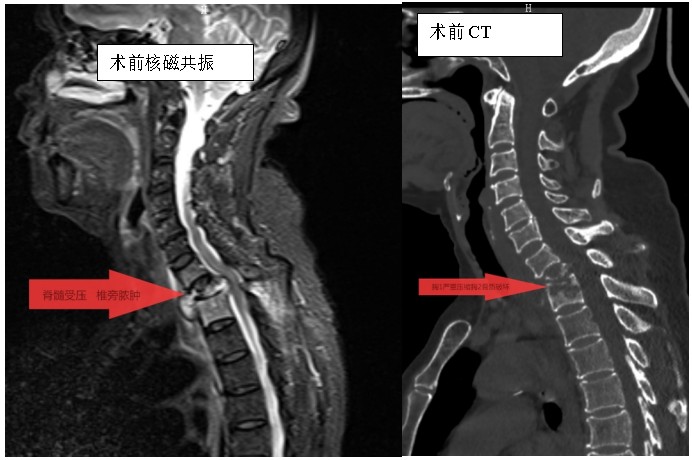

家住耒陽(yáng)的70歲的李奶奶,因“頸胸背部疼痛不適伴雙上肢麻木6個(gè)月”,來(lái)到衡陽(yáng)市中心醫(yī)院脊柱外科住院,住院當(dāng)天,患者頸胸椎核磁共振顯示:胸1、2椎體骨質(zhì)破壞,伴胸1、2椎旁軟組織腫脹、同層面椎管變窄,因脊髓受壓而導(dǎo)致頸胸背部疼痛。在錢(qián)軍博士帶領(lǐng)下,醫(yī)療團(tuán)隊(duì)詳細(xì)予以完善相關(guān)檢查后,研究患者的臨床資料,考慮脊柱結(jié)核并椎旁膿腫的可能性大,由于患者胸1椎體病理性骨折并椎管狹窄,遂囑患者嚴(yán)格臥床休息,術(shù)前給予標(biāo)準(zhǔn)四聯(lián)抗結(jié)核藥物治療2周,以控制活動(dòng)性結(jié)核感染,降低術(shù)中播散風(fēng)險(xiǎn),并嚴(yán)密監(jiān)測(cè)肝腎功能及血常規(guī)情況。